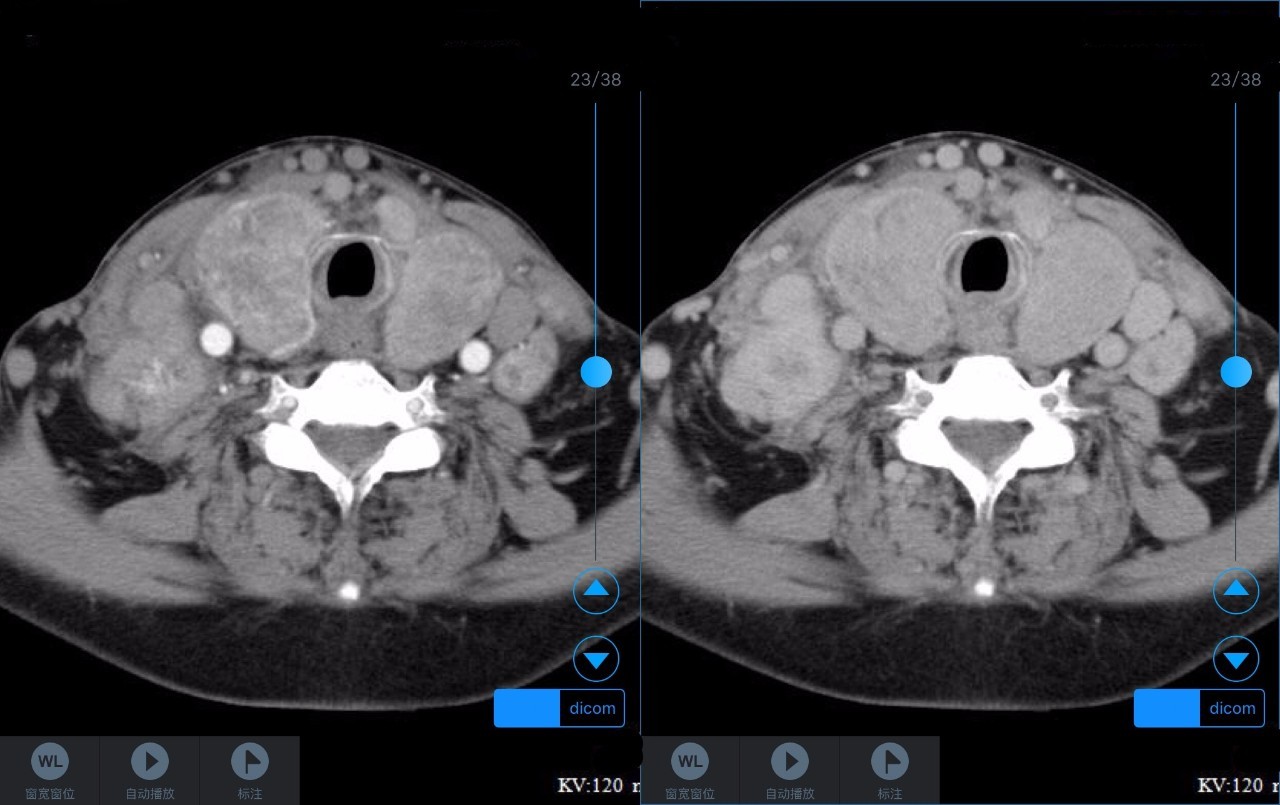

▼患者CT平扫(右)及增强CT(左)检查报告资料

Z主任 甲状腺肿大,内见弥漫多发结节,界限不清,甲状腺包膜毛糙。双侧颈部、锁骨上、纵隔多发肿大淋巴结,病变均强化明显,密度不均,边缘毛糙,考虑甲状腺恶性肿瘤伴多发淋巴结转移,或甲状腺内也是转移瘤。Castleman病多灶者少见,一般病变边缘光整,也不会累及甲状腺。建议穿刺活检。 C主任 双侧甲状腺肿大,密度不均,不均匀强化,甲状软骨未见明显骨质破坏气管右侧壁受压;双侧颈部多发肿大淋巴结,不均匀强化;考虑为甲状腺恶性占位性病变伴双侧颈部淋巴结转移,建议组织学进一步检查。 声明:以上资料均来自和缓名医平台的真实案例,为保护用户隐私,均用化名代替。资深医师Z咨询反馈